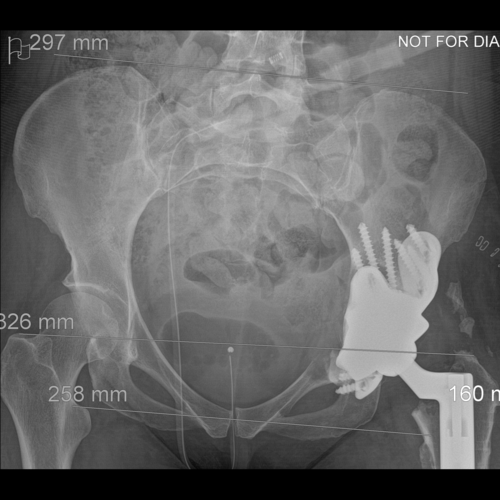

Anteroposterior and lateral plain radiographs demonstrate radiographic features of osteolysis around the acetabular and femoral components. Zara was asymptomatic.

Coronal CT - This is used by the surgeon and the biomedical engineer to design the custom implant specifically to the patient’s acetabular bone stock. This CT demonstrates significant loss of bone stock relating to the left hip resurfacing.

Anteroposterior plain radiograph showing the implant in situ with the surgical clips and a urinary catheter.

Coronal CT showing that the acetabular component is properly seated and the screws are within the bone.

Anteroposterior and lateral plain radiographs taken 6-weeks after the operation. Zara was able to bear some weight on her leg with the use of two crutches. Her wound healed well and she was able to raise a straight leg.

Anteroposterior and lateral plain radiographs taken 6-months after the operation. Zara was able to walk without support; she had a good range of movement and was pain free. Her cobalt level was 11.3ppb and chromium level was 21.0ppb – a huge reduction.

Anteroposterior plain radiograph taken at 1-year after the operation. There is no evidence of implant migration. Zara remained pain free and was very happy with the result of her new hip.